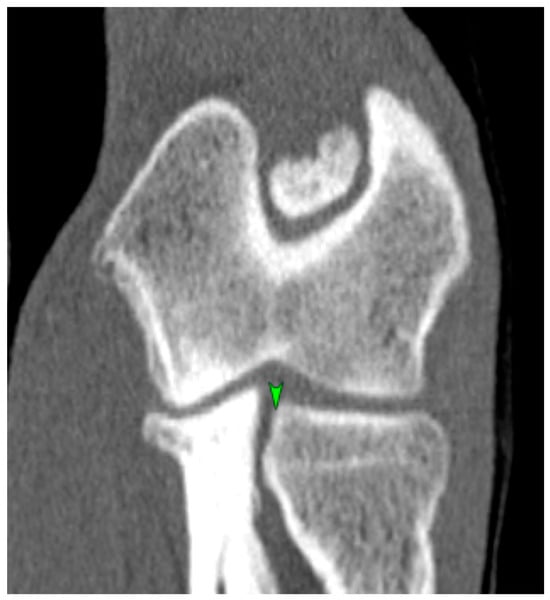

Is a Bacteriophage Approach for Musculoskeletal Infection Management an Alternative to Conventional Therapy? -